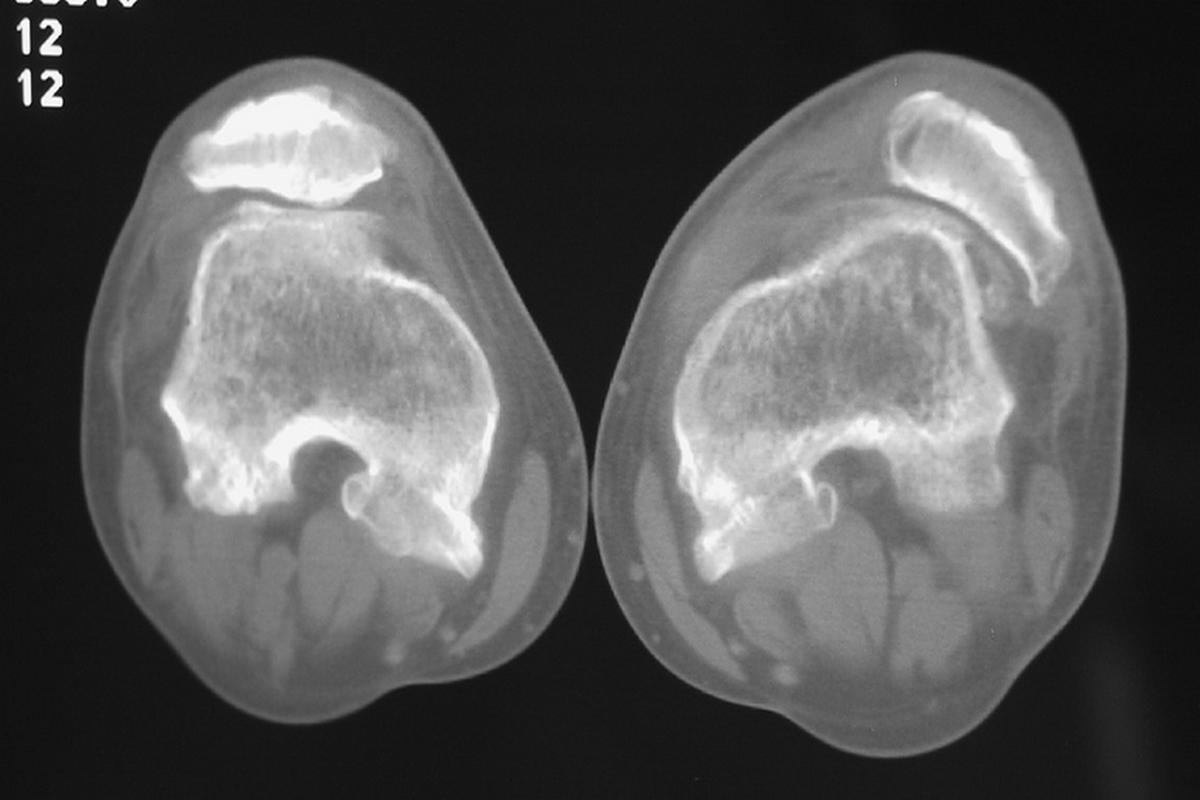

Η διάγνωση βασίζεται αρχικά στην κλινική εξέταση, όπου διαπιστώνεται η παραμόρφωση, η ευαισθησία και το αιμάρθρο. Οι ακτινογραφίες γόνατος είναι απαραίτητες για τον αποκλεισμό καταγμάτων και την εκτίμηση της θέσης της επιγονατίδας.

Η μαγνητική τομογραφία γόνατος αποτελεί σημαντικό διαγνωστικό εργαλείο, καθώς επιτρέπει την αξιολόγηση της ρήξης του έσω επιγονατιδομηριαίου συνδέσμου (MPFL), καθώς και πιθανών χόνδρινων ή οστεοχόνδρινων βλαβών.